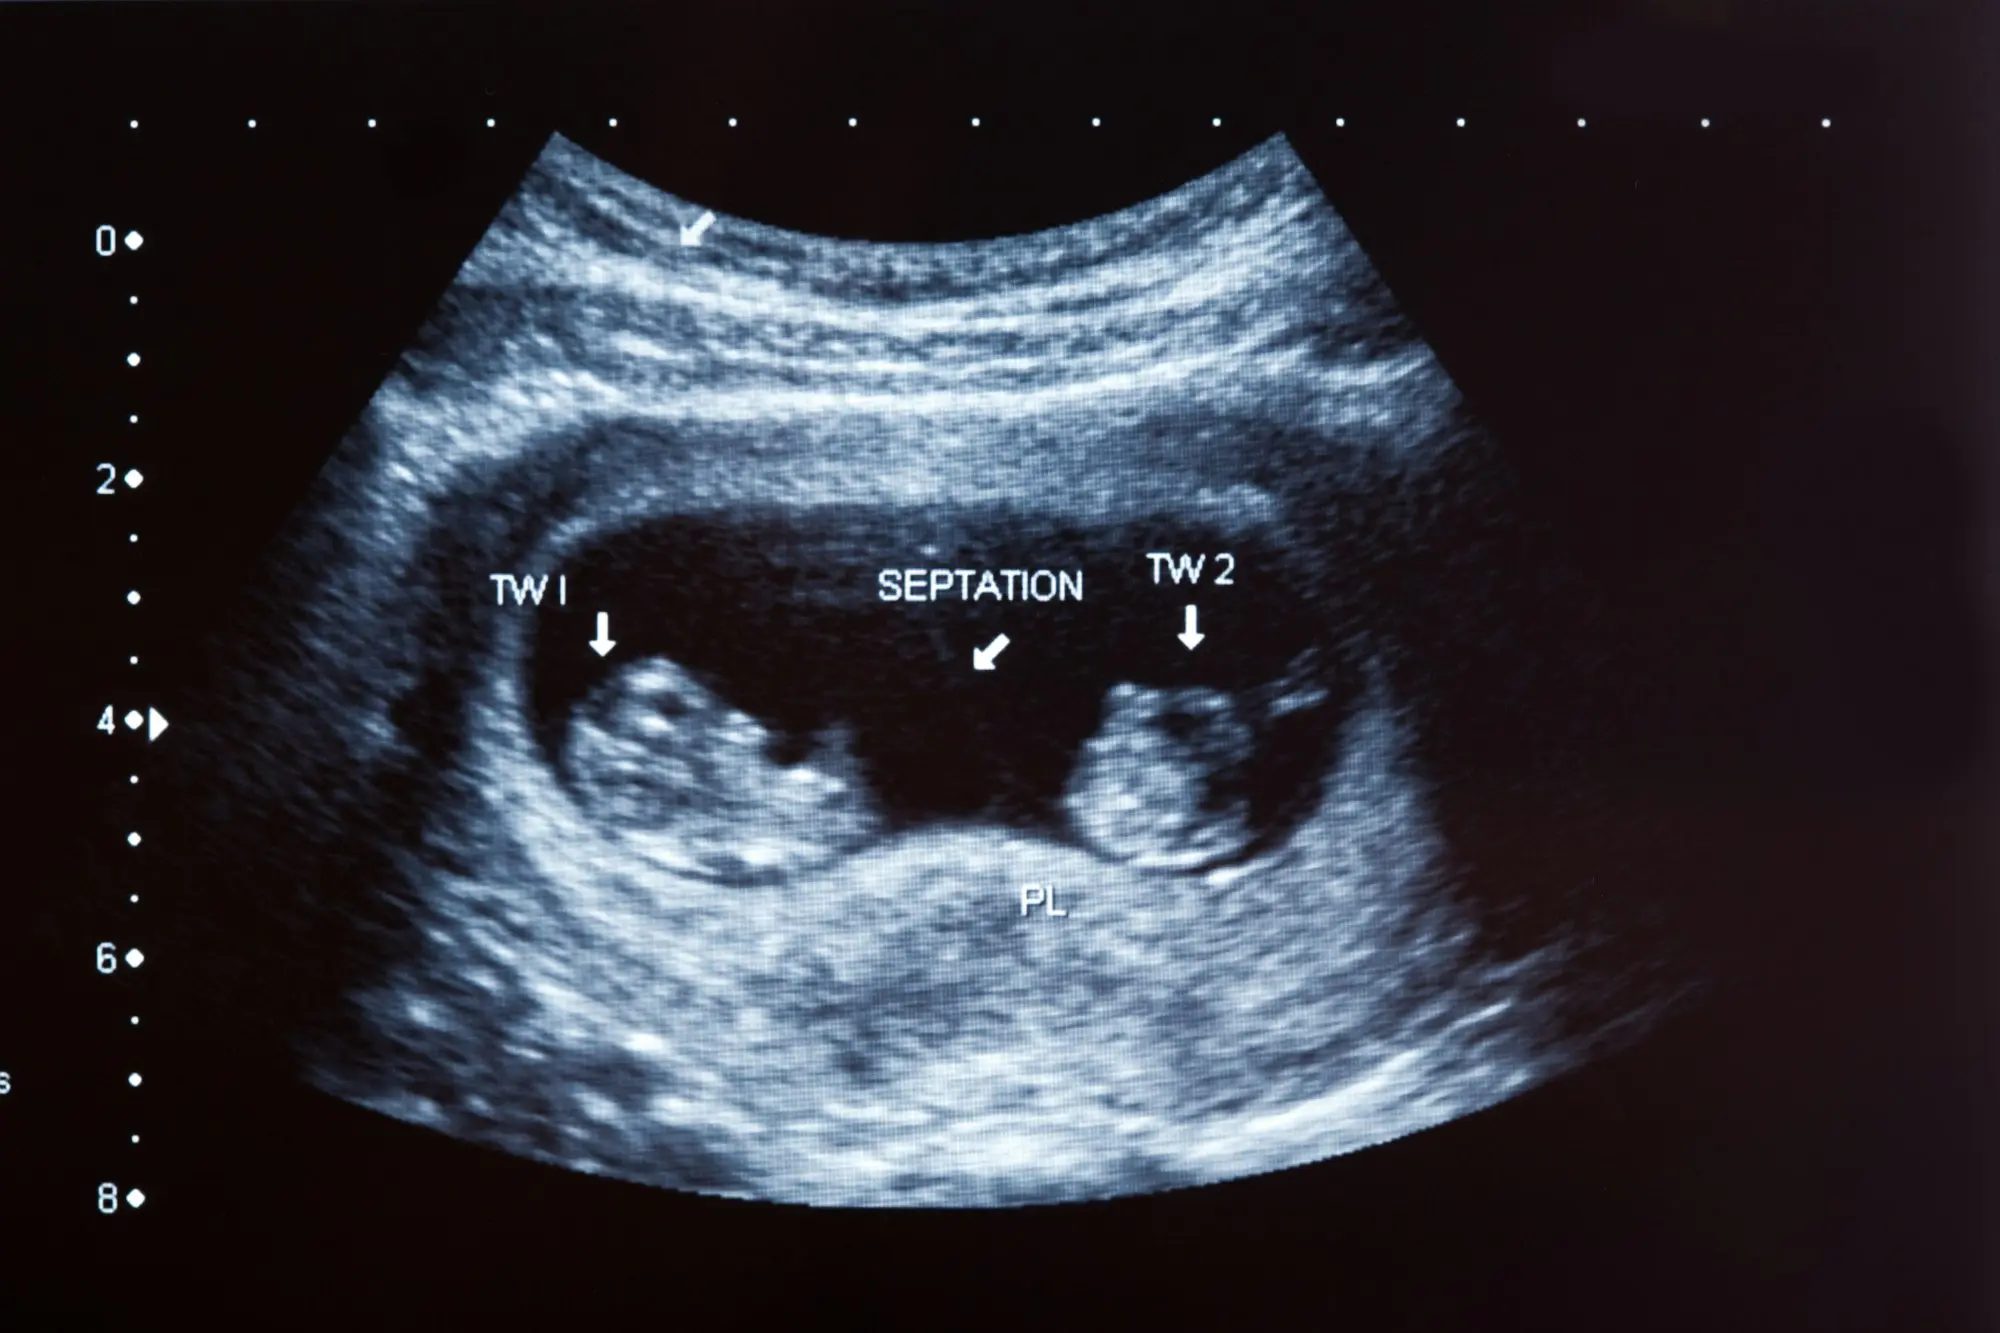

Detailed ultrasound scans to assess fetal development and identify any anomalies early, allowing for informed decision-making and planning.